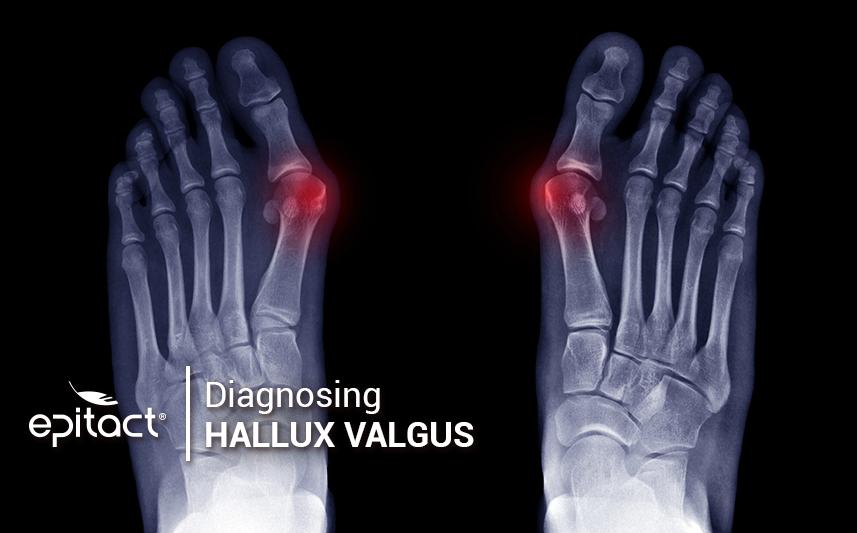

A radiological assessment aims to confirm the pre-diagnosis of hallux valgus. Il allows to precisely analyse the angle of deviation. Thanks to this, the doctor has all the necessary information to consider with serenity which curative or corrective options could be possible.

In addition, X-rays show the consequences of the hallux deviation on its neighbouring toes but also on the whole structure of the foot. An X-ray of both foot from the top allows to observe the deformity angle. Several X-ray images must be taken to determine the proper moment for surgery or the other treatment options. Moreover, an X-ray is to be taken of both foot on the dorsal-plantar surface (from the top), weigh-bearing and in schuss, i.e. with the knees flexed at 30°.

Lastly, two further images are required: one barefoot, in profile and weight-bearing, the other to assess and observe the sesamoid bones (from the front, weight-bearing, also called the Guntz view).